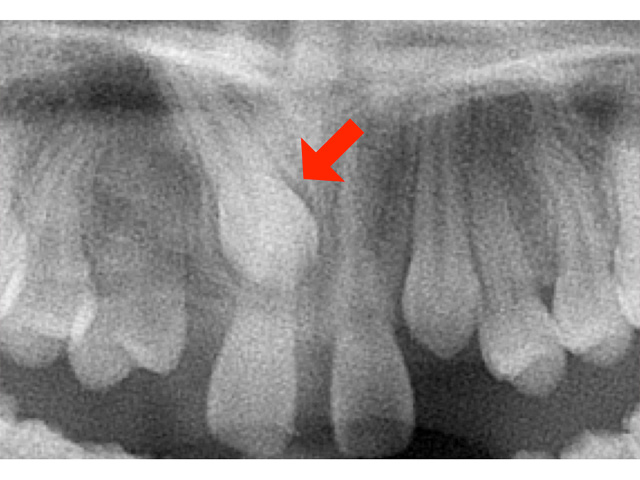

前歯の広いすき間に悩んで当院を受診されました。永久歯が2本不足する上に、向かって左上の犬歯が骨の中に完全に埋まっていました。